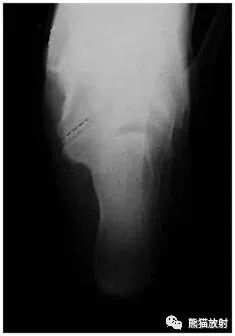

足正侧位平片

MR矢状PD压脂、矢状T1WI;主要表现:跟骨和舟骨之间可见骨性联合,MR上相应区域无水肿